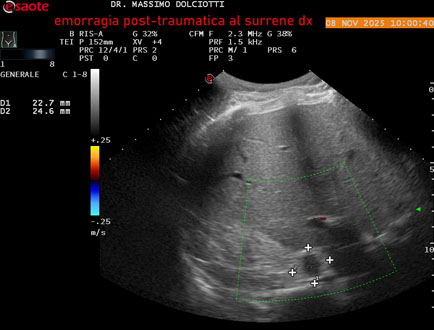

Data inserimento: 10/11/2025

Ecografia del: 08/11/2025

Strumento: Esaote MyLab Eight

Sonda: Convex Multifrequenza 1-8 MHz

Età Paziente: M 49 anni

Motivazione dell'esame: follow up per emorragia al surrene destro post-traumatica (incidente stradale).

Commento all'esame: le immagini ed il video documentano in sede surrenalica destra, formazione ipo-anecogena, a margini definiti, ovalare, delle dimensioni di 38,6 x 19,7 mm, da ricondurre ad emorragia post-traumatica.

Conclusioni: emorragia post-traumatica al surrene destro (post-traumatic hemorrhage to the right adrenal gland).

Presentazione: Dr. Massimo Dolciotti - Ancona

Elaborazione digitale: Andrea Dini - Ancona